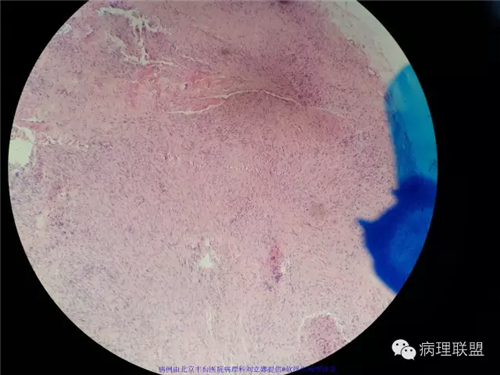

男性,61岁,右手掌腱膜挛缩。

送检:掌腱膜

同意诊断为掌纤维瘤病。掌纤维瘤病与足纤维瘤病同属表浅型纤维瘤病,表浅型纤维瘤病是发生于手掌和足底软组织的纤维母细胞增生性病变,以浸润性生长为特征,有局部复发的倾向,但不转移。该病例从临床表现上看就已经能作出掌纤维瘤病的诊断了,镜下改变为典型的掌纤维瘤病的形态。临床上掌纤维瘤病易累及成人,随年龄增长发病率迅速升高,罕见<30岁的患者。男性患者是女性的3-4倍。而足底纤维瘤病发生于儿童和青少年的比例很高。虽然足底病变更多见于男性,但发病率的性别差异不象手掌纤维瘤病那么明显。掌纤维瘤病发生在手的掌面,可引起掌指关节屈曲性挛缩,从而影响手功能,因此,掌纤维瘤病又称为Dupuytren挛缩。